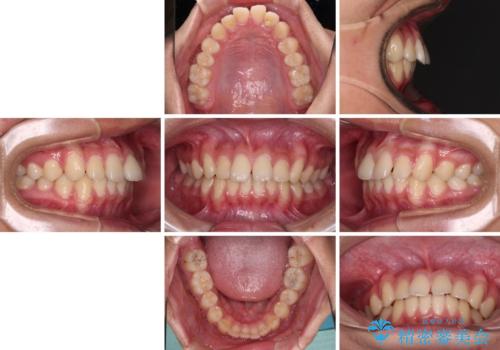

- 前歯のデコボコと隙間を気にして来院された高校生の患者様です。

下顎前歯が上顎前歯を突き上げるような咬み合わせとなっており、その影響で上顎正中に隙間ができている状態でした。

叢生の程度は軽度であり、本人もしっかりと使用する自信があるとのことだったので、インビザラインによる矯正治療を行うこととしました。

突き上げによる隙間を予防する為に、深い咬み合わせを改善するような治療計画としました。咬み合わせを改善させることはできましたが、隙間は後戻りしやすいので、通常の下顎前歯のみではなく、上顎前歯2本もワイヤーで保定を行いました。

高校生ということで、非常に短期間で治療を終えることができました。